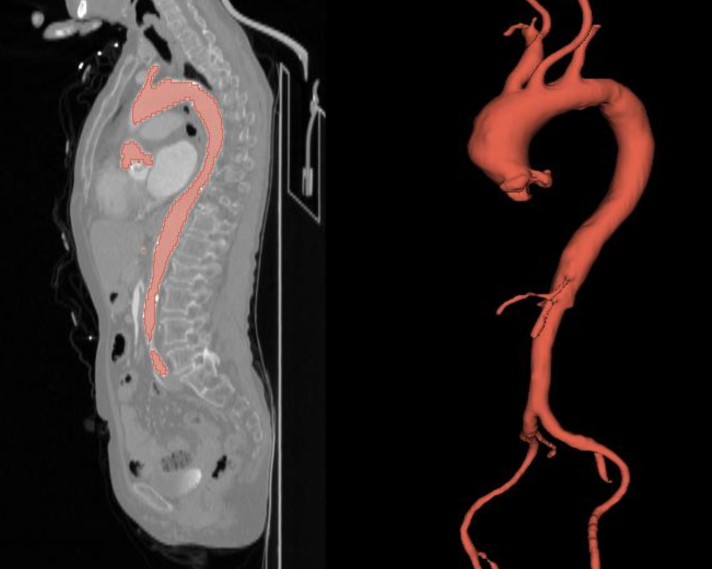

All ground truth masks were manually created following these steps. Firstly, the CTA data (.nrrd files) were visualized using 3D Slicer (https://www.slicer.org/) [31], enabling side-by-side and fused views of the medical images. Pre-processing was applied to reduce image noise for segmentation. Gradient anisotropic diffusion, known for its edge-preserving properties, was used, with the parameters listed in Table 3. Local thresholding was applied based on manually defined threshold ranges. The GrowCut [32] algorithm was then used for coarse segmentation of the aortic vessel tree. Finally, manual post-processing was performed to refine the segmentation and create the final AVT masks (.seg.nrrd file). A representative example of one CTA image with the AVT mask is provided in Figure 6.